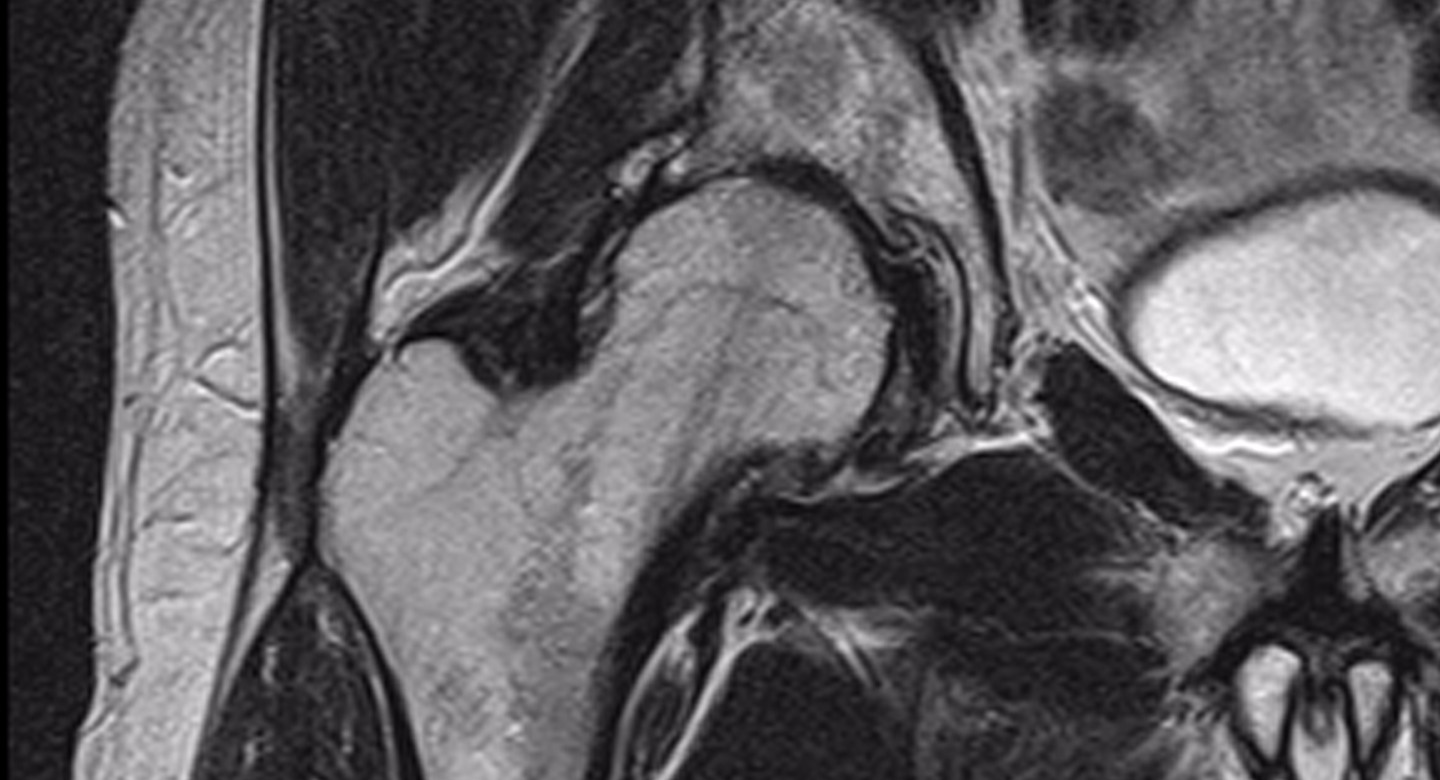

Improve your approach to Hip Imaging

Get access to Medality's Hip Imaging library with microlearning videos, expert case reviews, case stacks and quizzes designed to help you gain confidence in your diagnosis and improve turnaround times.